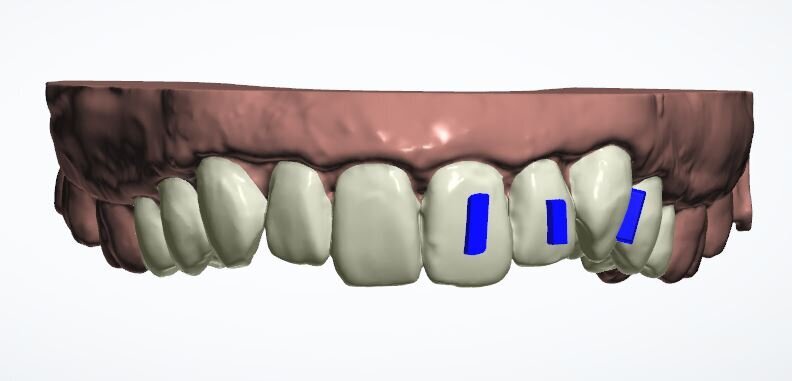

Two weeks later, the colour and contour of the patient’s gingival margins were as healthy as could be considering the crowding of the teeth. We discussed what treatment with ClearSmile Aligners would involve, such as interproximal reduction (IPR), compliance and risks, and a referral for specialist orthodontics was offered. Preferring to proceed with clear aligners, the patient signed off his full consent, and a two-stage putty impression was taken using a separation wafer. The Archwize digital planning software was used to predict tooth movement and necessary IPR throughout treatment. It suggested that 18 maxillary aligners would be needed.

Fig. 13a: Current position

Fig. 13b: Three refinement aligners

Fig. 13c: Six refinement aligners